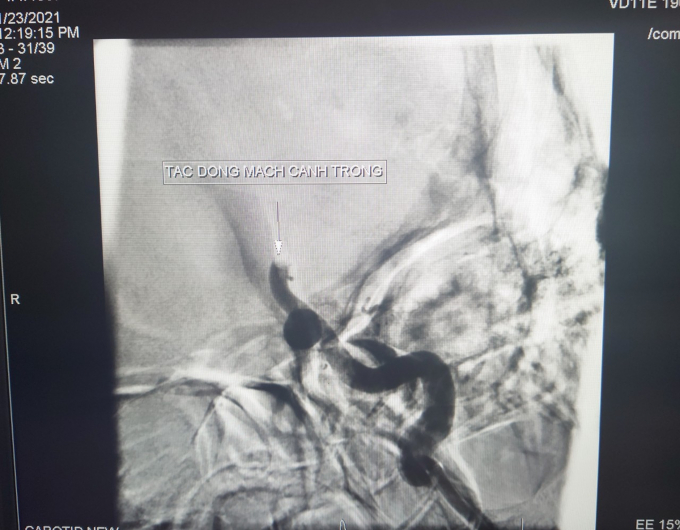

Hình ảnh tắc động mạch cảnh trong trái (DSA) trước can thiệp.

Trên hình ảnh CTscan não cho thấy vùng hoạt tử não chưa nhiều, khả năng vẫn còn có thể cứu được vùng não xung quanh vùng hoạt tử. Hình ảnh CTscan mạch máu não cho thấy mạch máu bị cục máu đông gây tắc từ động mạch cảnh trong trái đoạn ngoài sọ đến động mạch não giữa trong sọ. Ê kíp vẫn quyết định can thiệp cho bệnh nhân sau khi đã đánh giá lợi ích và nguy cơ.